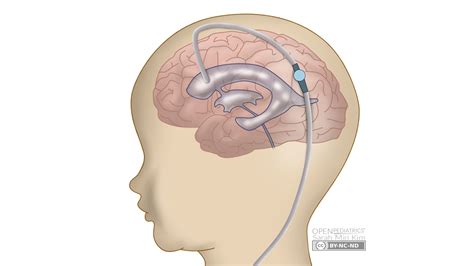

Hydrocephalus is a condition characterized by the accumulation of CSF in the brain, leading to increased intracranial pressure. This can cause a variety of symptoms, including headaches, nausea, and cognitive impairments. A VP shunt is a surgical solution that helps manage this condition by redirecting the excess fluid to the abdomen, where it can be absorbed naturally.

The VP shunt consists of several components:

• A catheter placed in the ventricles of the brain to drain the CSF.

• A valve that regulates the flow of CSF.

• A distal catheter that directs the fluid to the peritoneal cavity.